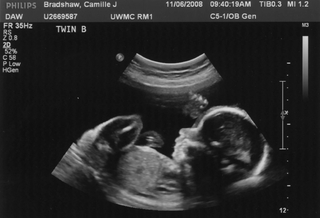

Можно ли заранее узнать вес ребенкаНа деле — не особо. Врачи на осмотрах измеряют живот, проверяют положение ребенка, делают УЗИ, но все эти методы дают лишь приблизительное представление. Часто будущих мам пугают «слишком крупным плодом», а на деле ребенок рождается обычного размера. Даже современные исследования показывают, что более чем в половине случаев прогнозы УЗИ о «гигантском малыше» оказываются ошибочными.

Иногда УЗИ ошибаются с размером ребенка. Источник изображения: dishcuss.com